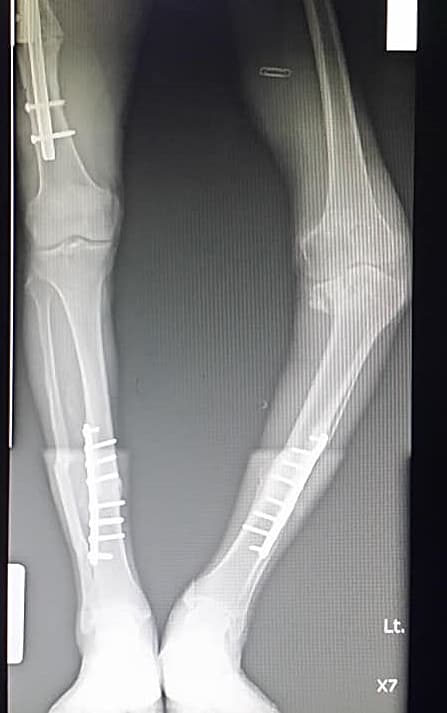

วันนี้หมอสุนทร ขอพูดคุย พร้อมด้วยการยกเคส น่าสนใจเคสหนึ่ง มาให้อ่านกันครับ เป็นเคส ข้อเข่าเสื่อม ที่ผู้ป่วย เคยได้รับอุบัติเหตุอย่างรุนแรงมาก่อน ตั้งแต่วัยรุ่น ( ดูจากภาพฟิล์มที่นำมาแสดง ) ใน ภาพเอกซเรย์ แสดงให้เห็นว่ามีการผ่าตัดใส่เหล็กอยู่ข้างในอย่างมากมาย พูดง่ายๆ ข้างในข้อเข่าผ่านการกรำสงครามมาหลายศึกยิ่งนัก

แน่นอนครับว่าเคสนี้ ข้อเข่าด้านซ้าย น่าจะเคยเกิดอุบัติเหตุมาก่อน และทำให้กระดูกหัก ประกอบกับ ไม่ได้รับการรักษาอย่างถูกต้อง ร่วมกับภาวะขาอีกข้างหนึ่ง (ขวา) ที่หักอย่างรุนแรง และหมอคนก่อน จำเป็นต้องทำให้ขาสั้นลง คาดว่าน่าจะมีกระดูกสูญหายไปพอสมควร เมื่อขาขวาสั้นลง ขาซ้ายจึงยาวกว่า และนี่คือผลที่เกิดขึ้นในระยะยาว ด้วยข้อเข่าข้างซ้ายต้องรับน้ำหนักมากขึ้น มีผลทำให้ข้อเข่าซ้ายทำงานหนัก เมื่อเดินใช้งานมากๆ ก็จะทำให้เกิดการ “พัง” ของข้อเข่าอย่างรุนแรง เพราะข้างซ้ายต้องรับน้ำหนักมากกว่า

เมื่อหมอเจอผู้ป่วย และทำการซักประวัติในครั้งแรก ต้องขอแสดงความเคารพในความอดทนของผู้ป่วยเหลือเกิน เพราะจากภาพเอกซเรย์ ซึ่งบ่งบอกถึงอาการที่สาหัสมาก แต่ผู้ป่วยยังคงทำงาน กรีดยาง ทำงานสวน ซึ่งต้องใช้ความอดทนกับความเจ็บปวดมานานกว่า 10 ปี ความอดทนและแข็งแกร่งของผู้ป่วยท่านนี้ หมอซูฮก (นับถือ) จริงๆ ( แต่ไม่ควรอดทนนานเกินไปนะครับ )

1. การใช้ข้อเข่าเทียม จะต้องเป็นรุ่นพิเศษ คือ จะต้องมีแกน เพื่อฝังลงไปลึกในตัวโพรงกระดูกเพื่อให้มั่นใจได้ว่าข้อเข่าจะมั่นคงและแข็งแรงจริงๆ

3. ผ่าตัดเหล็กเดิม เพื่อเคลียร์พื้นที่ นอกจากนี้แล้วคนไข้ยังเคยมีเหล็กที่เคยใส่ไว้ที่หน้าแข้งด้านซ้าย ซึ่งเหล็กนี้เองจะเป็นสิ่งที่ขวางแกนข้อเข่าเทียมที่จะใส่ลงไป หมอเลยจำเป็นจะต้องผ่าตัดเพื่อเอาเหล็กออกก่อนและเคลียร์พื้นที่ในครั้งที่ 1